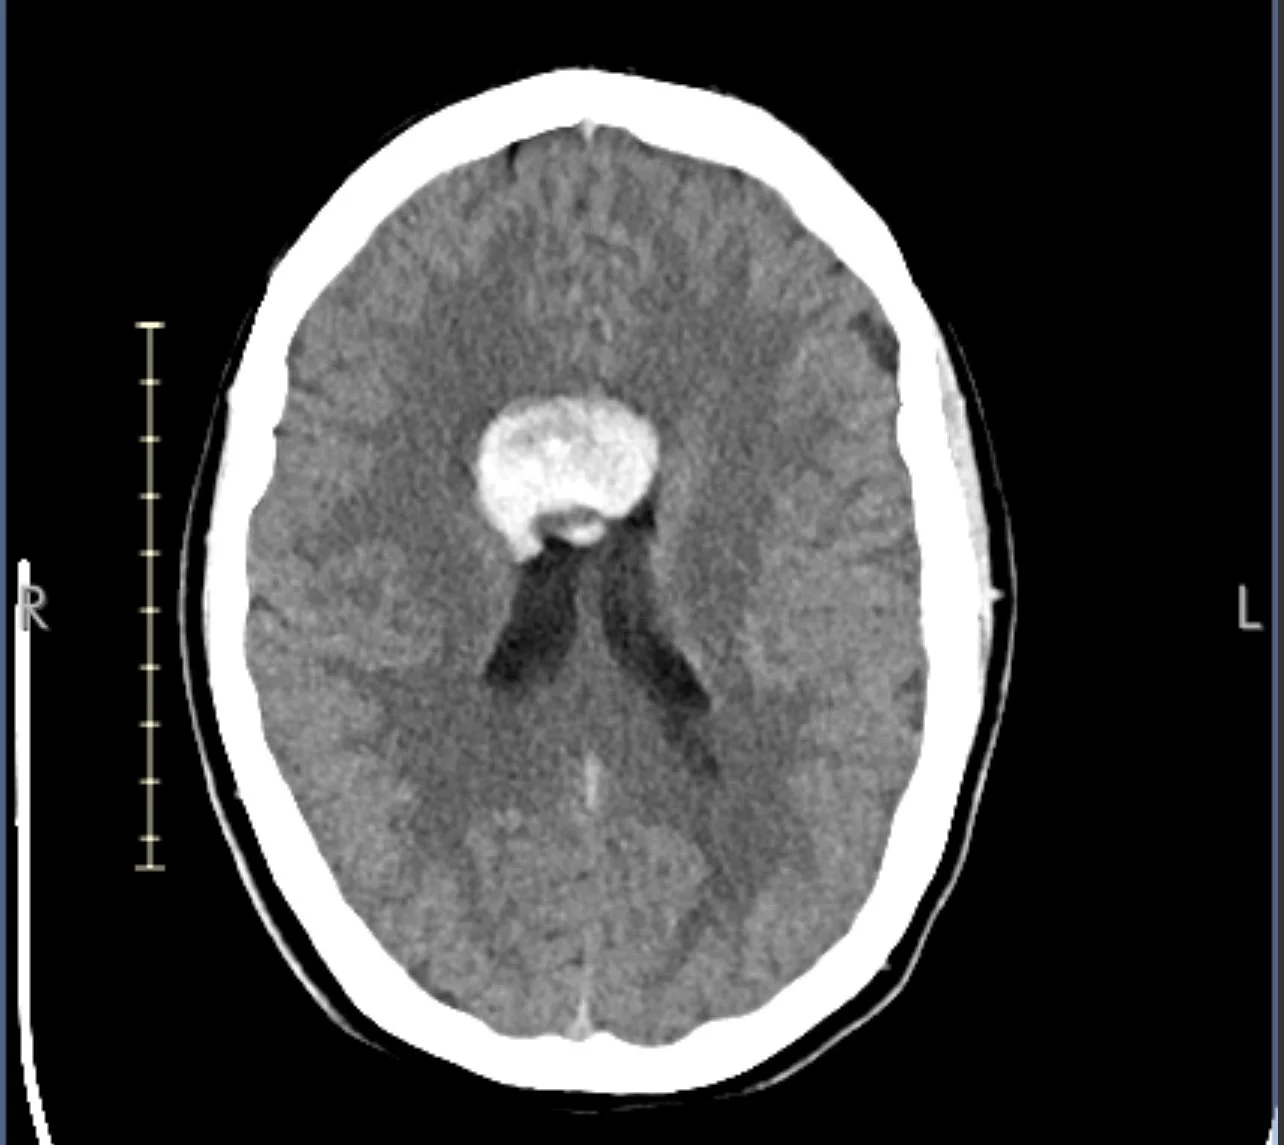

On April 10, surgeons removed a vascular malformation located in the ventricular space near the hypothalamus and pituitary region — the regulatory axis for hormones, stress response, and inflammatory signaling. I returned home April 12.

Vascular Malformation

April 12, 2025